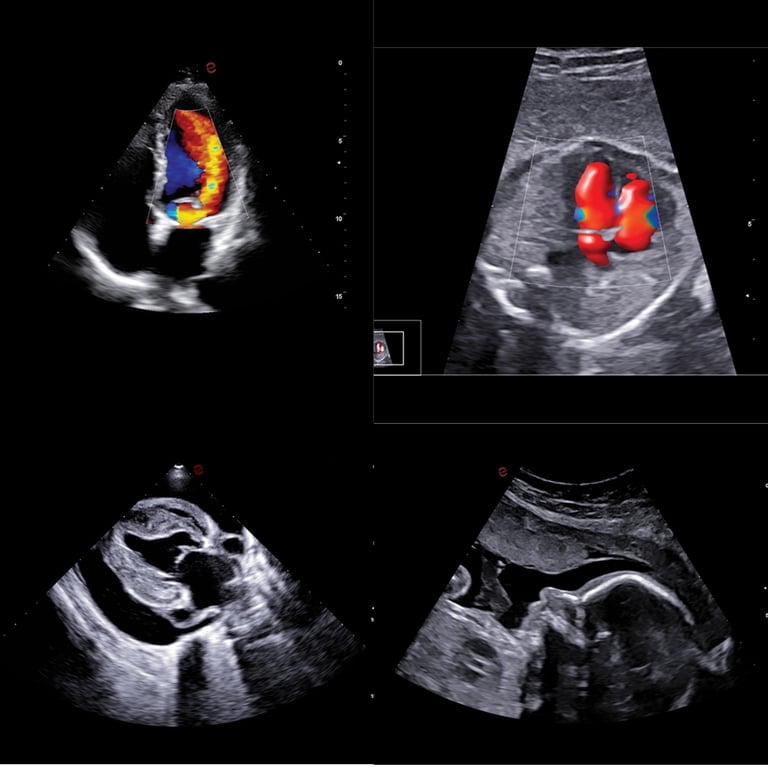

Kardio — Exklusiv

XStrain™ 2D · AutoEF · TDI

XStrain™ 2D für dedizierte myokardiale Deformationsanalyse — Longitudinal-, Radial- und Zirkumferential-Strain. AutoEF KI-gestützte Ejektionsfraktion. TDI (Tissue Doppler Imaging). Herzinsuffizienz-Evaluation direkt im Praxisalltag — auf neuem Niveau.

Frauen & OB

3D/4D · Women's Health · eDetect

3D/4D für pränatale Diagnostik mit unübertroffener Klarheit. Vollständiges Women's Health Package: Gynäkologie, Brust, Geburtshilfe. eDetect KI-Läsionserkennung. CnTI™ Kontrastverstärkung für Leber-Charakterisierung.

Kardio-FeaturesXStrain™ 2D, AutoEF, TDI, AutoCM

Phased Array · ExklusivP1-8AKardiologie · XStrain™ optimiert

MyLab A70 XStrain Kardio-Analyse